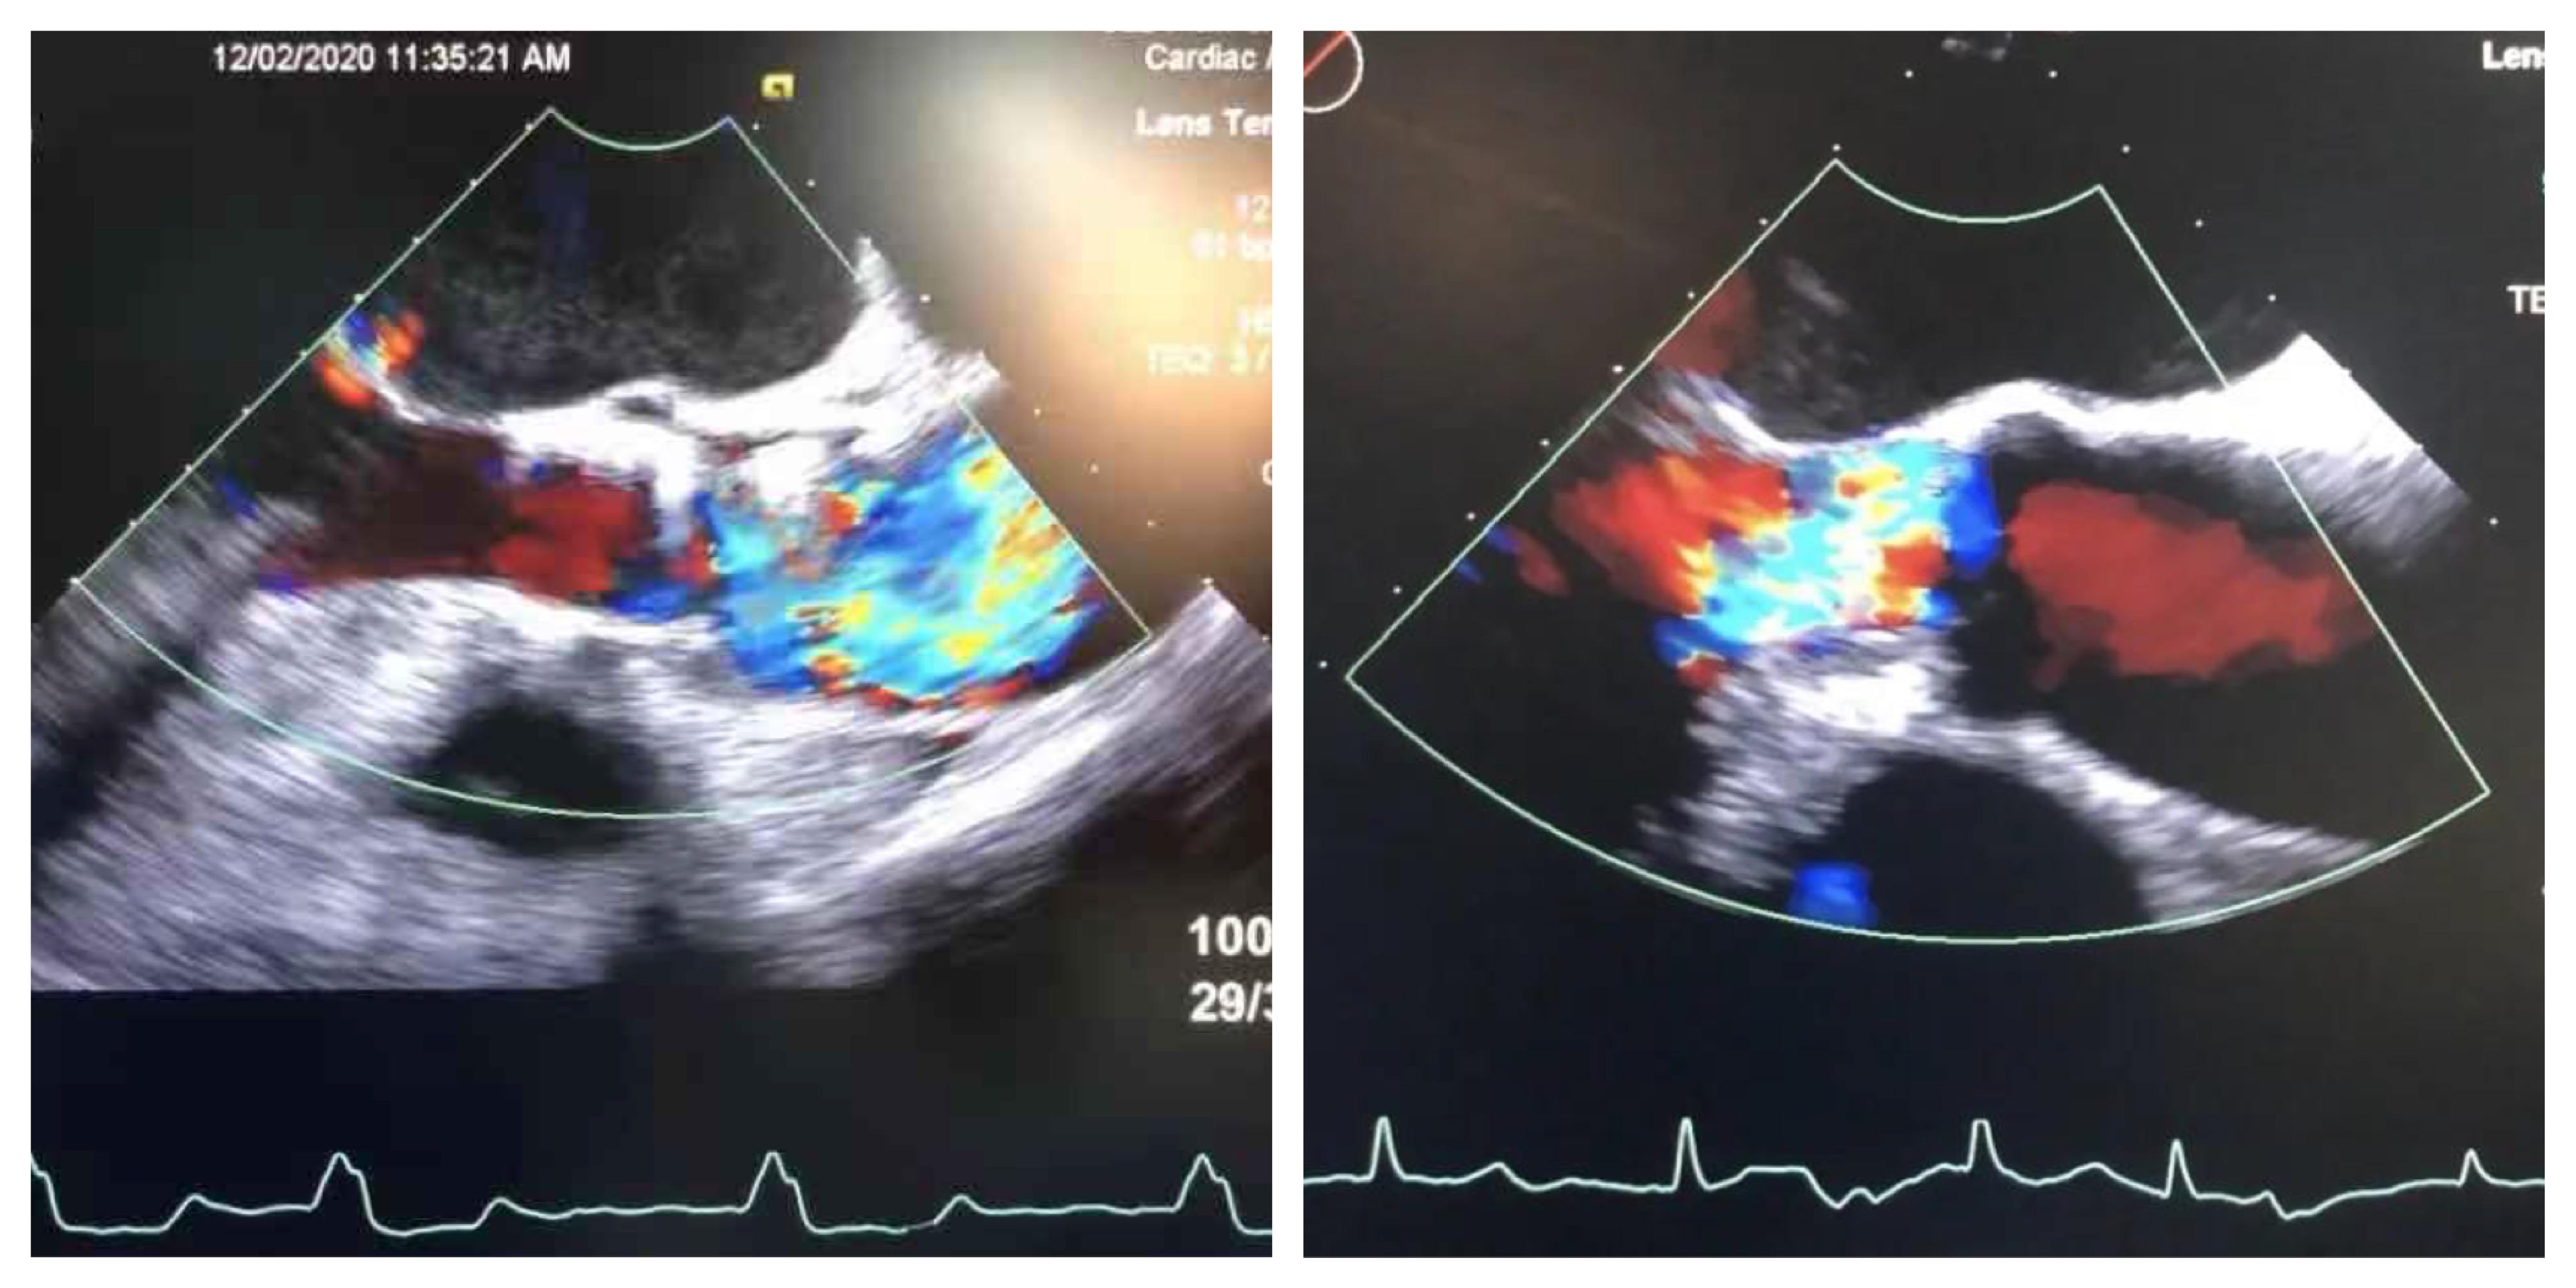

术后即刻:无瓣周漏,舒张压明显改善至68mmHg

术前心超 术后心超